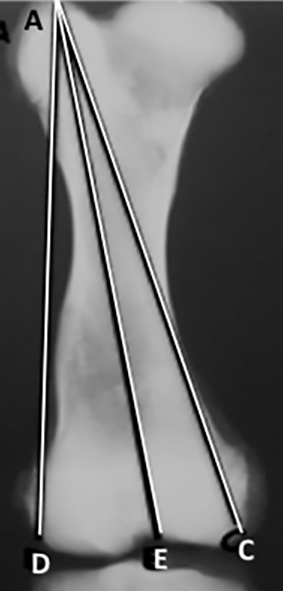

Se realizaron radiografías, antero-posterior y lateral de los fémures y las tibias, postmortem de los miembros inferiores. Las radiografías fueron medidas. En las radiografías antero-posterior del fémur se trazaron y midieron 6 líneas (Figura 1).

Figura 1: Radiografía de fémur antero-posterior. Líneas desde la punta del trocánter mayor. A-D: a la región más lateral del cóndilo lateral. A-E: al intercóndilo. A-C: a la región más medial del cóndilo medial.

(Figura 2): 1. A-D: desde la punta del trocánter mayor a la región más lateral del cóndilo lateral. 2. A-E: desde la punta del trocánter al intercóndilo. 3. A-C: desde la punta del trocánter a la región más medial del cóndilo medial. 4. B-D: desde el centro de la cabeza a la región más lateral del cóndilo. 5. B-E: desde el centro de la cabeza al intercóndilo.  6. B-C: desde el centro de la cabeza a la región más medial del cóndilo medial.

Figura 2:Radiografía de fémur antero-posterior. Líneas desde el centro de la cabeza. B-D: a la región más lateral del cóndilo. B-E: al intercóndilo. B-C: a la región más medial del cóndilo medial.